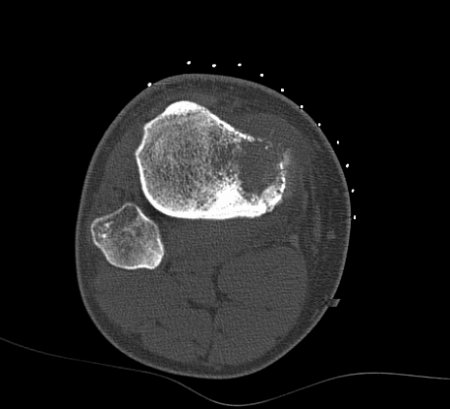

Computed tomographic scan, axial view; osteosarcoma of proximal tibia; matrix production and bone destruction are best appreciated on conventional tomographs

Personal collections of Dr Michael J. Klein and Dr Luminita Rezeanu